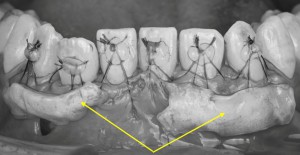

※下顎前歯の拡大写真

下あごの前歯部に注目すると、黒い線で示した部分が歯の上の部分(歯冠)と根の部分(歯根)の境目になります。

この境目よりも歯ぐきが下がっている状態がみられ、歯ぐきの退縮が起こっていることが確認できます。

※下顎の前歯の拡大写真

丸で囲った部分に注目すると、歯の根の形が歯ぐきの下にうっすらと浮き出て見える状態が確認できます。

このような所見は、歯ぐきや骨の厚みが比較的薄い可能性を示していると考えられます。

また、矢印で示した部分では、歯と歯の間の歯ぐき(歯間乳頭)がやや下がっており、**すき間が見える状態(いわゆるブラックトライアングル)**が認められます。

このように歯と歯の間の歯ぐきにも変化がみられる場合には、治療方法の選択や処置の内容を慎重に検討する必要があり、症例によっては外科的な処置が難しくなることがあります。